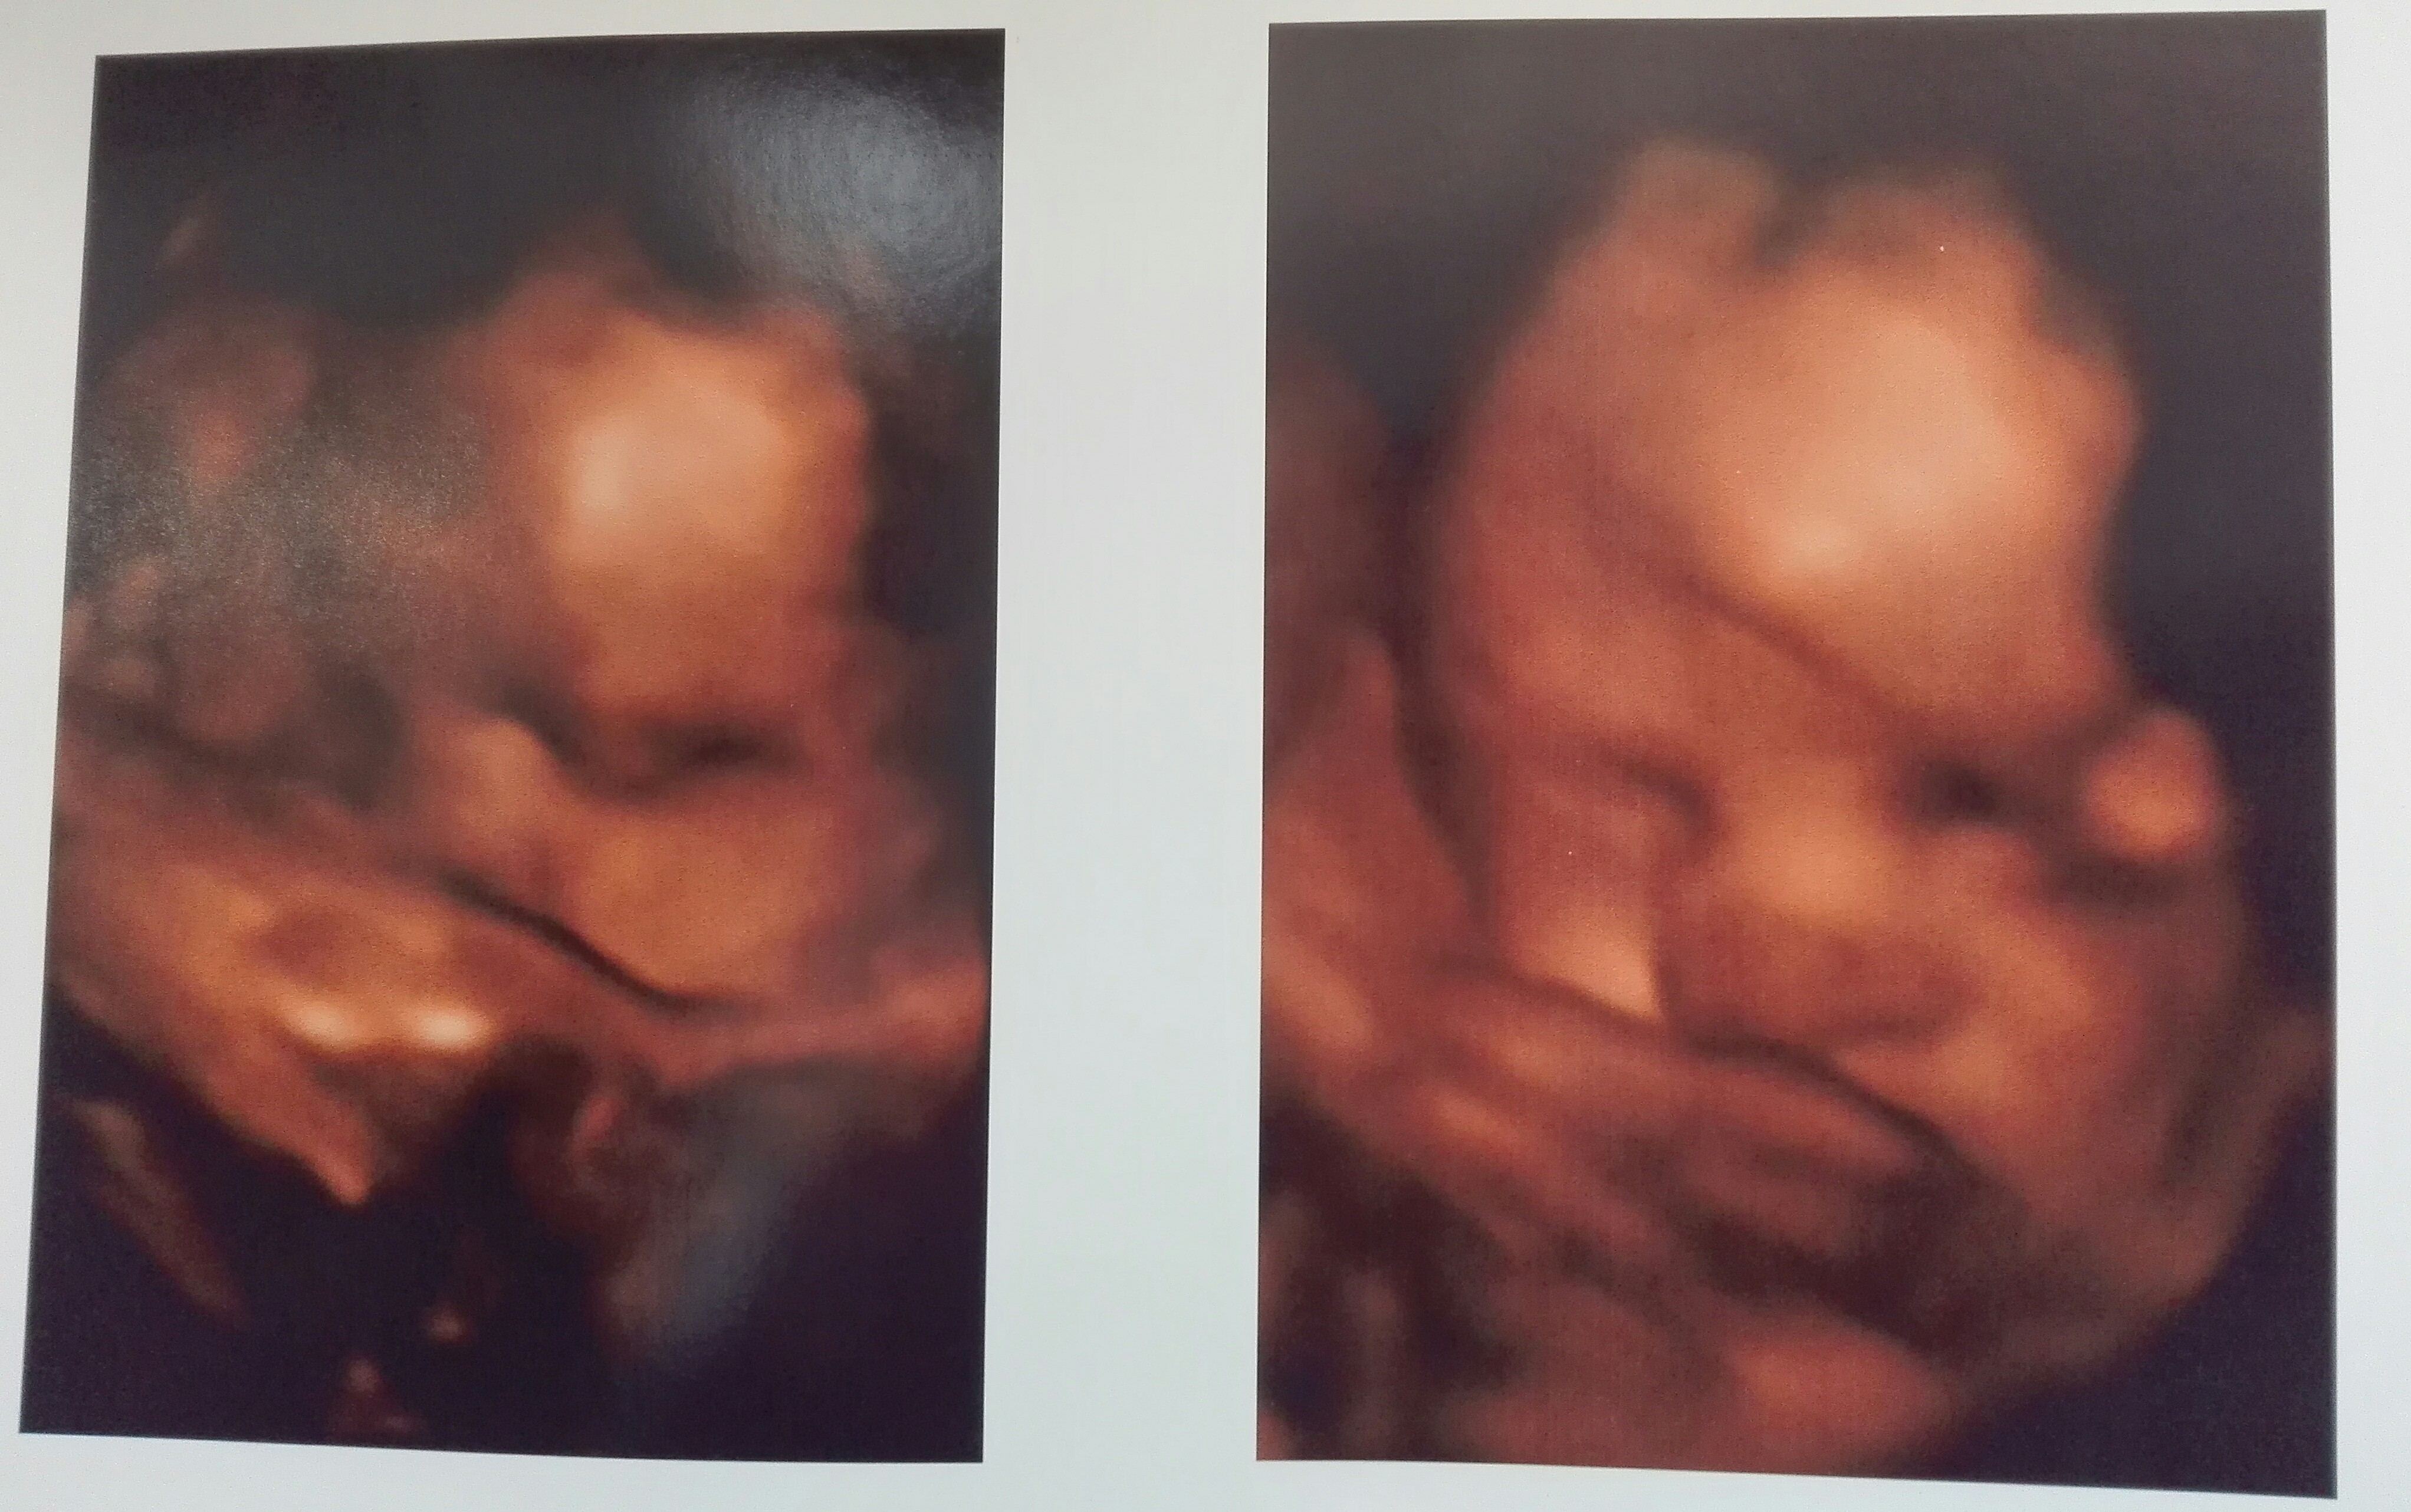

Jestem po wizycie. 30+4. Moja kluseczka wazy juz 1803. Piekna jest i zdrowa, ale sie ciesze ;)

IMG_20190126_191638.jpg